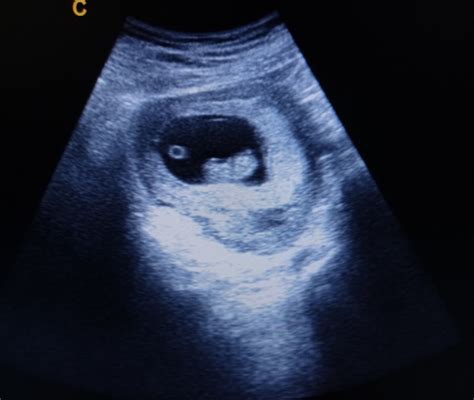

Molte donne con inserzione velamentosa del cordone ombelicale potrebbero non manifestare sintomi evidenti. I sintomi più comuni includono battito cardiaco fetale anomalo, sanguinamento vaginale e segni di travaglio pretermine. Il sanguinamento vaginale durante la gravidanza e il rallentamento della frequenza cardiaca fetale, tuttavia, possono indicare anomalie nel cordone ombelicale e nella placenta. La diagnosi di inserzione velamentosa del cordone ombelicale inizia in genere con una valutazione clinica approfondita. Un'ecografia dettagliata è lo strumento principale per diagnosticare l'inserzione velamentosa del cordone ombelicale. Durante i controlli ecografici di routine durante la gravidanza, i medici possono vedere se il cordone ombelicale si sia inserito nella posizione sbagliata. Viene utilizzato anche l'imaging Doppler. Studi scientifici hanno dimostrato che le ecografie in scala di grigi e color Doppler possono diagnosticare in epoca prenatale inserzioni anomale del cordone ombelicale e vasa previa. Un caso di studio ha esaminato tre casi di inserzione velamentosa di funicolo: la scala di grigi e il Power Doppler sono stati in grado di rilevare in epoca prenatale l'inserzione velamentosa di funicolo in tutti e tre, e ciascun caso è risultato in un cesareo senza complicazioni.